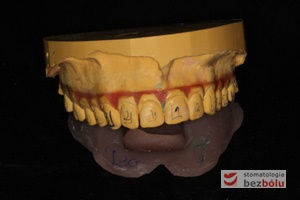

- Wykonanie specjalistycznego modelu poprzez odcięcie wyrostka zębodołowego i separacje poszczególnych zębów, a następnie zespolenie za pomocą wosku modelowego.

- Przesunięcie zębów, każdy ząb może być przesunięty maksymalnie o 0,4 mm.

- Ponowne powielenie modelu po ustawieniu zębów.